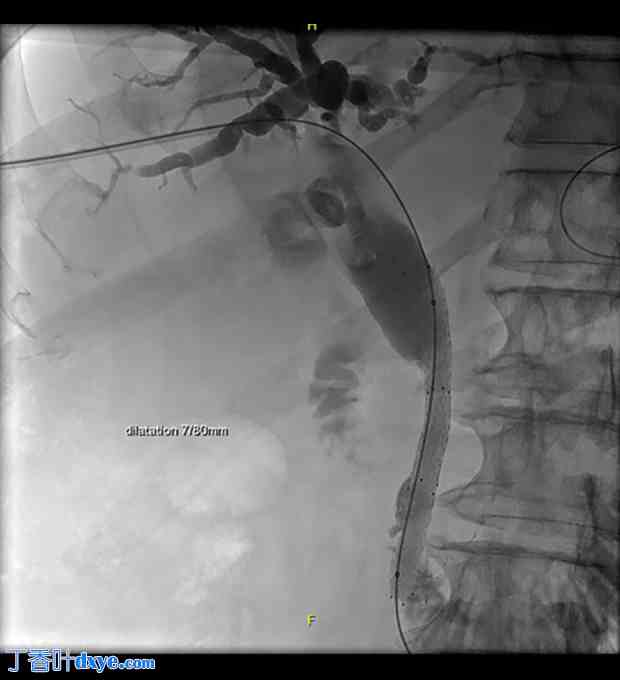

因此,作者不得不采用经皮肝穿刺胆道引流 (PTBD) 的放射学方法,但此举也遇到了一些障碍。患者的结肠明显位于肝脏和横膈膜之间,符合 Chilaiditi 征(图 3);因此,作者实施了联合手术,在腹腔镜下牵拉右结肠,以更好地暴露肝脏和胆道目标。腹膜探查提示肝脏胆汁淤积,并伴有轻微纤维化和硬化前期。将位于肝脏和横膈膜之间的右结肠牵拉至骨盆方向,并用可吸收编织缝线固定右结肠曲。随后可以安全进行 PTBD,然后放置金属胆道支架,手术进行得很顺利(图 4)。在腹腔镜探查过程中,作者发现了一个与肝静脉段相对应的小的白色病变,对其进行了活检以进行病理检查。PTBD 的定位导致胆红素值迅速下降,并提高了患者的舒适度。术后11天,患者出院,在家人的协助和护理下回家。

经皮肝穿刺胆道引流术及腹腔镜右结肠牵拉术后支架置入术。